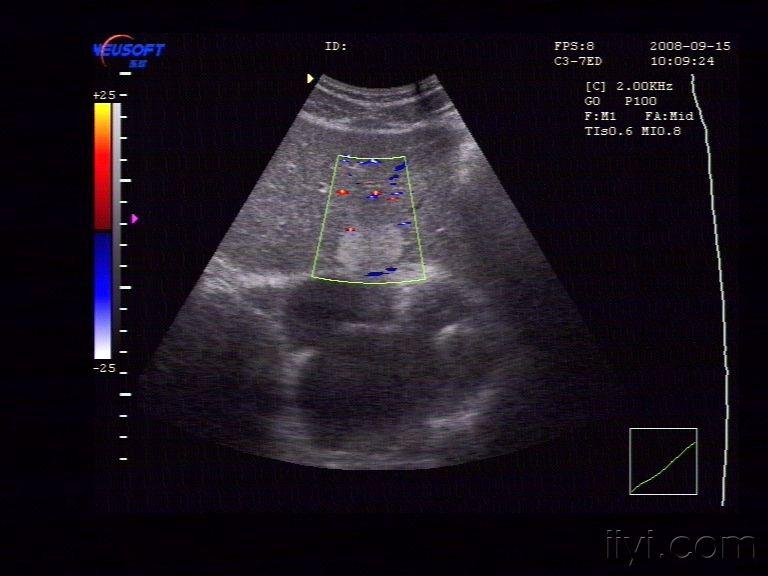

【贴图】肝脏血管瘤

体检发现左肝内一较强回声团,大小约为29X22X15mm,边界清,中央回声稍低。CDFI:未见异常血流信号